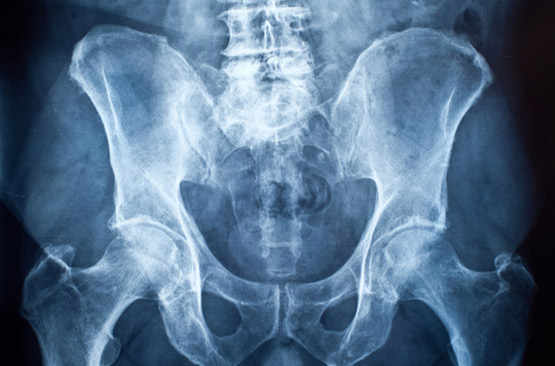

L'ostéoporose, une perte de densité osseuse liée au vieillissement, cause 9 millions de fractures annuelles.

Avec l’âge nous subissons tous une usure naturelle des os, mais passé un certain seuil, l’ostéoporose devient pathologique et peut entrainer des fractures...

L’ostéoporose touche 200 millions de personnes à travers le monde et principalement des femmes après 50 ans.

L’ostéoporose est une maladie chronique caractérisée par une diminution de la densité minérale osseuse...

Ostéoporose: quand les os se fragilisent